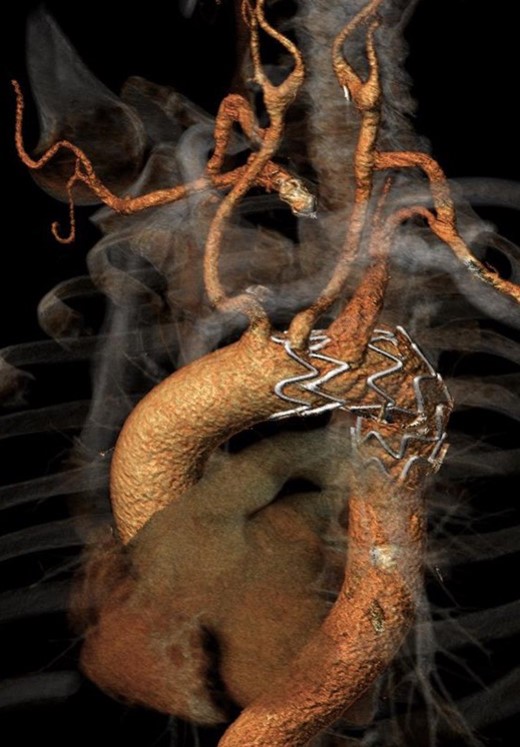

Twenty-two months after the procedure, the patient referred to our Unit due to the worsening of dysphagia. A new CT scan showed the enlargement of the aneurysmal sac (115 mm) due to the persistent Type II endoleak from bronchial arteries (Fig. 3). An endovascular embolization of the target vessels was not feasible due to the impossibility to cannulate the bronchial arteries without direct puncture. A preoperative esophageal endoscopy was performed to exclude the presence of esophageal–aneurysmal fistulas and an open repair with right thoracotomy and aneurysmorraphy of the AARSA was performed to occlude the bronchial side branches and to reduce the compression of the giant aneurysm on the esophagus (Fig. 4, 5). The postoperative course was uneventful and the patient was discharged on the 11th postoperative day.

Angio-CT scan at 22 months showing Type II endoleak with significant sac enlargement.